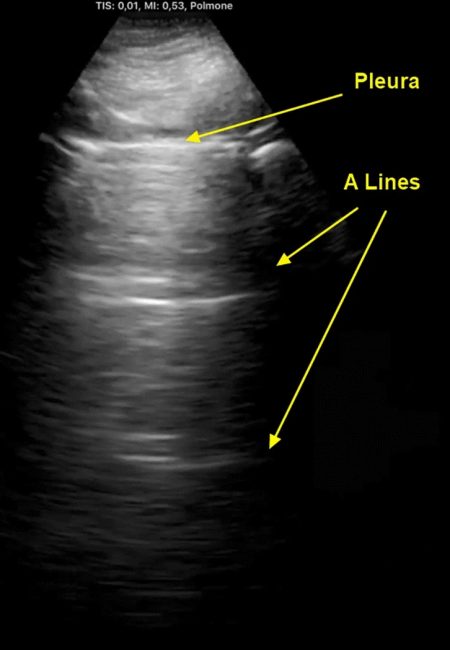

Horizontal arfifact(수평 허상)으로 알려지기도 한 A-line은 갈비뼈 음영들 사이에서 pleural line이 반복되는 모양으로 나타난다. A-line의 존재는 정상으로 간주되며, B-line이나 lung rockets(폐 로켓)이 모일 때는 관찰할 수 없다.

1. A-line은 skin-pleural line 간의 거리 간격만큼 정확히 떨어져서 나타난다.

Horizontal artifact (A-lines):

Horizontal echogenic line between rib shodows that represents the repetition of the pleural line. Seen in normal lung.